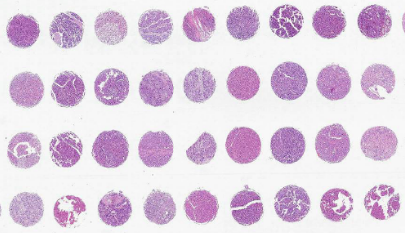

組織芯片制作步驟由普拉特澤生物病理實(shí)驗(yàn)平臺(tái)為大家分享,普拉特澤生物長期為廣大科研人員提供組織芯片外包代做服務(wù)。組織芯片是繼基因芯片、蛋白質(zhì)芯片之后出現(xiàn)的又一種重要的生物芯片,主要用于研究同一種基因或蛋白質(zhì)分子在不同細(xì)胞或組織中表達(dá)的情況。

1、芯片微陳列設(shè)計(jì):在構(gòu)建組織芯片之前,應(yīng)該預(yù)先計(jì)劃檢測多少樣本,然后相應(yīng)地進(jìn)行設(shè)計(jì)。對(duì)大多數(shù)研究來說,在一個(gè)常規(guī)的載玻片上放置60~100個(gè)樣本已經(jīng)足夠了。當(dāng)樣本超過100例時(shí),上樣、切片、染色及研究各個(gè)步驟都要求相當(dāng)熟練,并且由于樣本排列過于緊密,有可能導(dǎo)致芯片制作和研究失敗。因此在計(jì)劃檢測數(shù)百個(gè)到上千標(biāo)本時(shí)可考慮多做幾個(gè)組織芯片。

2、收集病例及相關(guān)蠟塊:挑選出具有隨訪資料的不同發(fā)展階段的腫瘤組織蠟塊,根據(jù)HE切片對(duì)石蠟標(biāo)本中有代表性的點(diǎn)進(jìn)行標(biāo)記,包括典型的腫瘤和相應(yīng)的正常組織,以構(gòu)建腫瘤組織芯片。

3、TMA受體蠟塊制備:取97.5克萊卡石蠟+2.5克蜂蠟(2.5%)混合,制成長36mm*寬26mm*高17mm的空白蠟塊,在該蠟塊20mm×16mm范圍內(nèi)設(shè)計(jì)10×8點(diǎn)組織陳列。組織四周預(yù)留0.5cm-0.7cm空間,用組織儀打孔制成TMA蠟塊。

4、在組織芯片制作機(jī)上用細(xì)針對(duì)受體蠟塊打孔,孔徑以1~1.5mm比較適宜。

5、同樣在供體蠟塊上標(biāo)記的相應(yīng)部位打孔采集組織芯??讖酵瑯訛?/span>1~1.5mm。

6、將組織芯轉(zhuǎn)移到受體模塊的孔中,每個(gè)組織芯之間的間距以0.2mm為佳。

7、為了防止在打點(diǎn)、切片、染色或免疫組化過程中出現(xiàn)漏點(diǎn),滑片及掉片現(xiàn)象,每個(gè)樣本可以上樣1-2個(gè)點(diǎn)。

8、將構(gòu)建好的TMA芯片蠟塊放在相宜的塑料盒子內(nèi),并嚴(yán)密固定防止移位。放入55℃溫箱中約10分鐘,在蠟將要完全溶解前,取出室溫下冷卻,使受體模塊的蠟與新插入的小圓柱狀組織溶為一體,取下蠟塊,于4℃冰箱中保存?zhèn)溆谩?/span>

9、切片前,蠟塊需在4℃中預(yù)冷4h左右,然后夾在切片機(jī)上進(jìn)行修正,等修到全部組織完整為止。用-20℃預(yù)冷冰袋貼在蠟塊上5-10min左右,快速連續(xù)切片30-50張左右,再用冰袋冷凍組織塊,或直接在冰凍切片機(jī)內(nèi)進(jìn)行,直至將組織切完為止。將4μm連續(xù)切片分別漂在涼水中,讓其自然展開,按順序?qū)⑶衅D(zhuǎn)移至45℃的溫水中展片2min左右,將其貼在浸有APES切片黏合劑的載玻片上晾干,60℃中烤片3min左右,58℃中繼續(xù)烤片18h,-20℃保存?zhèn)溆谩?br/>